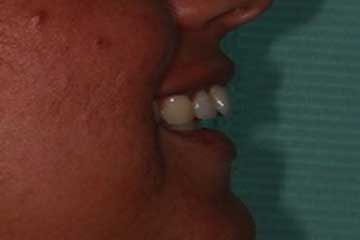

Riabilitazione gnatologica, ortodontica ed estetica

Durata del trattamento: un anno